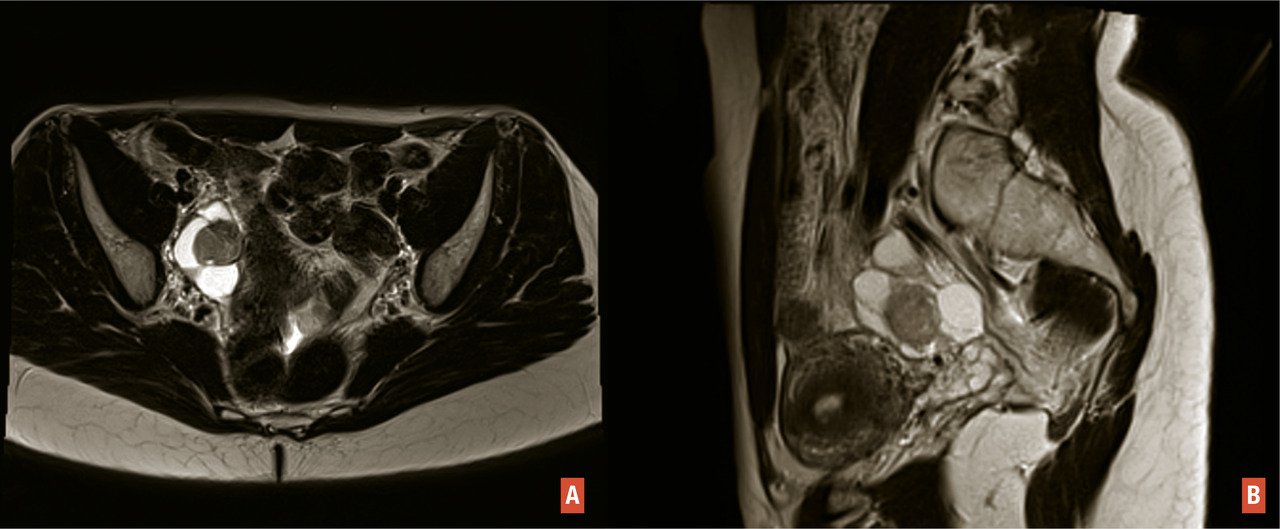

Les femmes porteuses de l’une de ces mutations sont à haut risque de cancer colorectal et de l’endomètre non endométrioïde [fig. 1 A et B], et à risque plus modéré de développer un cancer des ovaires (endométrioïdes ou à cellules claires) [fig. 2 A et B], de l’intestin grêle, des voies excrétrices urinaires, des voies biliaires et de l’estomac. Le spectre restreint regroupe les cancers du côlon, du rectum, de l’endomètre, de l’intestin grêle et des voies urinaires. Le spectre élargi inclut les autres types de cancer.